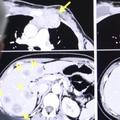

Pevka skupine Girls Aloud, Sarah Harding je na Twitterju sporočila srce parajočo novico. 38-letnici so v začetku letošnjega leta diagnosticirali raka na dojki, ki se je sedaj razširil tudi na druge dele telesa. Povedala je, da ima trenutno vsak teden kemoterapijo in da se bori na vse pretege.

"Upam, da ste v teh negotovih časih vsi varni. Tukaj nisem že dolgo objavljala, hvala vsem, ki ste mi pisali, da bi preverili, kako je z mano, to mi ogromno pomeni. Čutim, da je sedaj pravi čas, da delim, kaj se dogaja z mano. Ni lahkega načina, s katerim bi lahko to povedal. V začetku leta so mi diagnosticirali raka na dojkah, pred nekaj tedni pa sem prejela še žalostno novico, da se je rak razširil tudi na ostale predele mojega telesa. Razumem, da je morda šokantno, da to berete na družbenih omrežjih, a to res ni moj namen, a ker je bilo prejšnji teden omenjeno, da so me videli v bolnišnici, čutim, da je pravi čas, da ljudem povem, kaj se dogaja in to se mi zdi najboljši način," je v odkritem tvitu zapisala pevka, ki se je v zapisu še zahvalila za vso podporo družine, prijateljev in medicinskega osebja, obljubila, da bo oboževalce obveščala o svojem zdravju in vse skupaj prosila, naj spoštujejo njeno zasebnost.